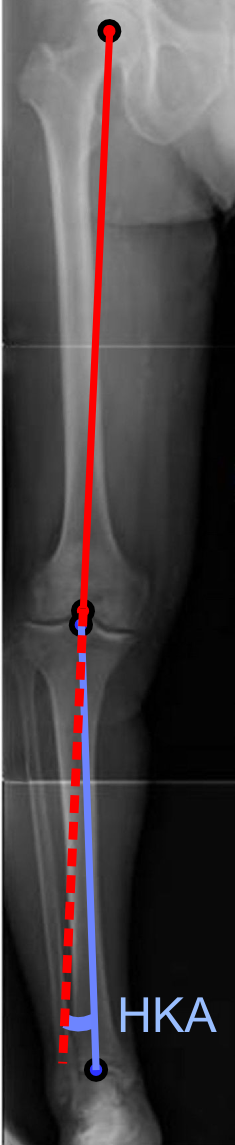

투사 방사선 촬영법에서 내반슬 또는 외반슬 변형 정도는 발목 관절 중심과 넙다리뼈의 기계적 축 사이 각도인 '엉덩이-무릎-발목 각도'[7][8]로 정량화할 수 있다. 성인은 정상적으로 에서 1.5° 사이의 내반슬을 보이나,[9] 소아의 정상 범위는 다르다.[10]

3. 1. 엉덩이-무릎-발목 각도

투사 방사선 촬영법에서 내반슬 또는 외반슬 변형의 정도는 ''엉덩이-무릎-발목 각도''[7]로 정량화할 수 있는데, 이는 발목 관절의 중심과 넙다리뼈의 기계적 축 사이의 각도이다.[8] 성인의 경우 정상적으로 에서 1.5° 사이의 내반슬을 보인다.[9] 소아의 정상 범위는 성인과 다르다.[10]